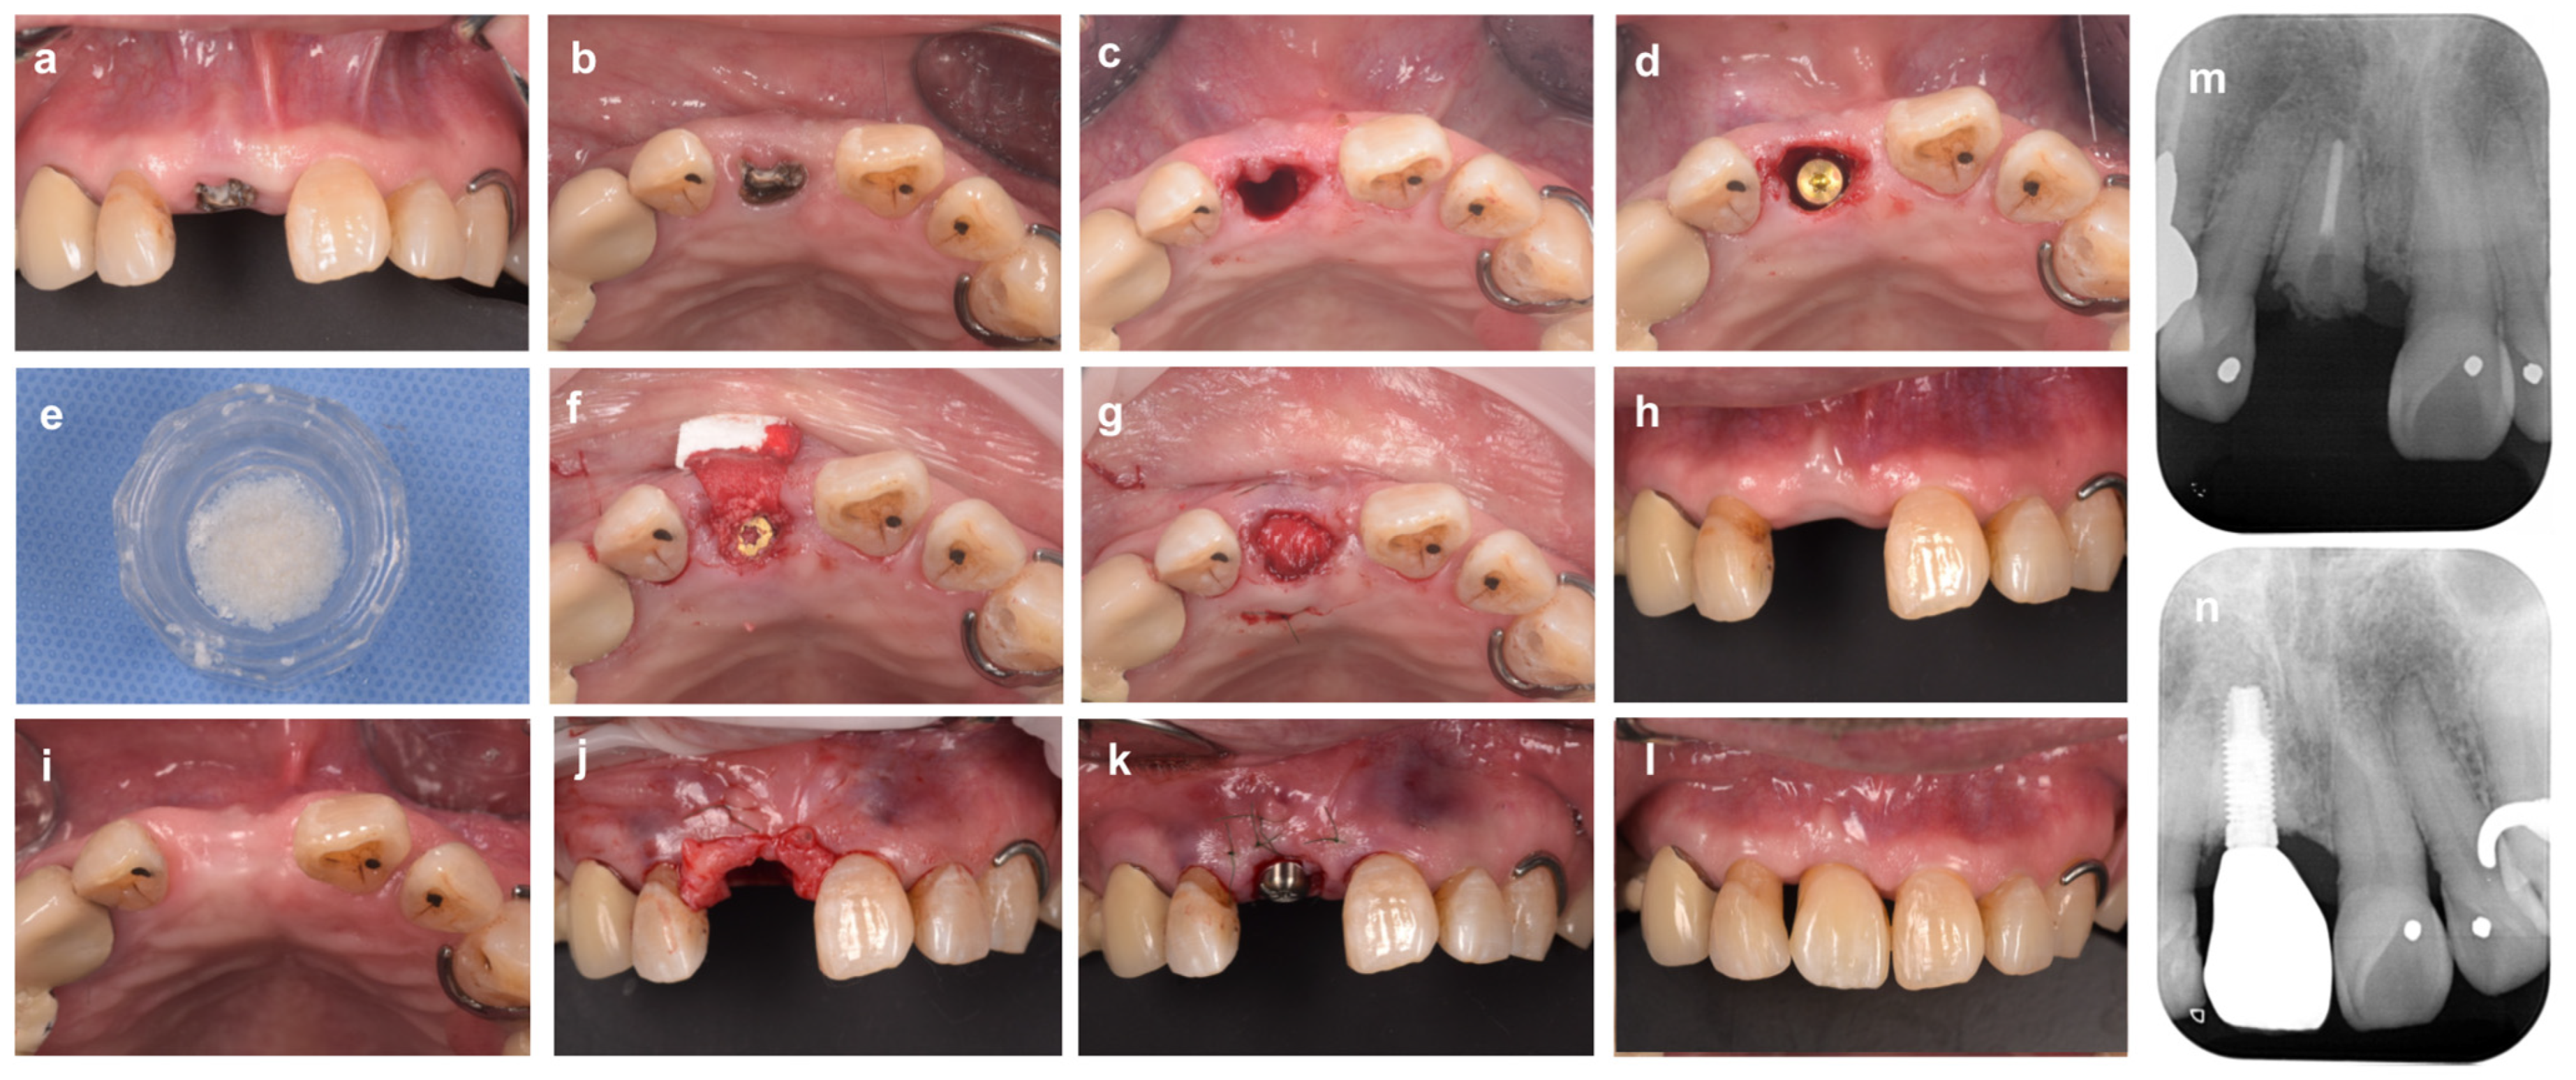

Clinical Case of Immediate Extraction Implant Placement with Bone Grafting

Clinical Cases of Alveolar Ridge Preservation Using Soft Tissue or Alternative Membrane Material

Clinical Cases of Alveolar Ridge Preservation with the Open Membrane Approach Using Non-Absorbable Membranes